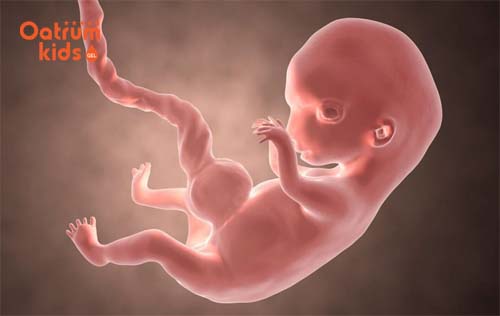

Bước sang thai tuần thứ 9 là lúc bé yêu đã có hình dáng của một con người, đã mất đuôi và phát triển cơ quan nội tạng. Lúc này bé có kích thước như một trái ô liu, độ dài khoảng hơn 2,5cm một chút được tính từ chóp đầu cho đến mông và bé nặng chưa đến 7gram.

Cũng ở thời điểm này bé yêu gần như đã hoàn thành xong phần quan trọng nhất trong quá trình sự phát triển của mình. Nói cách khác giai đoạn 9 tuần tuổi này là khởi đầu của giai đoạn bào thai, khi mà các mô lẫn cơ quan ở bên trong cơ thể của bé đã phát triển và trưởng thành một cách nhanh chóng. Qúa trình phát triển diễn ra như sau:

- Thai 9 tuần tuổi cũng là thời điểm mà cơ thể của bé đã bắt đầu chuyển động được, điển hình như tất cả các khớp chính của bé đang hoạt động như khuỷu tay, cổ tay, vai, khớp đầu gối và cả mắt cá chân… đã hoạt động tốt.

- Đặc biệt hơn lúc này cổ tay của con yêu đã có thể tự gập lại và bé biết đặt tay lên tim. Đồng thời đôi chân của bé cũng đã đủ dài để có thể gấp lại ở trước bụng.

- Thêm vào đó khuôn mặt bé cũng đã hình thành rõ mũi, lỗ mũi và miệng. Vì vậy nếu siêu âm với thiết bị hiện đại mẹ sẽ thấy rõ được khuôn mặt.

- Đôi mắt của con yêu ở giai đoạn 9 tuần tuổi cũng đã được hình thành hoàn toàn nhưng mí mắt bé vẫn nhắm chặt, bé không mở ra cho tới khi được 27 tuần.

Thai được 9 tuần tuổi đã biết cử động chân tay, đặt tay lên ngực.

Nhìn chung khi thai 9 tuần tuổi hình dáng cột sống của bé đã có thể hiện rõ thông qua làn da trong mờ, đồng thời các dây thần kinh cột sống cũng đang bắt đầu căng ra từ tủy sống. Đặc biệt trán bé lúc này vẫn tạm thời phình ra bởi vì não con đang phát triển và nằm ở vị trí cao trên đầu, vì thế mẹ sẽ thấy trán bé chiếm nửa chiều dài cơ thể con. Tính từ đỉnh đầu đến mông thì bé dài tầm hơn 3cm.